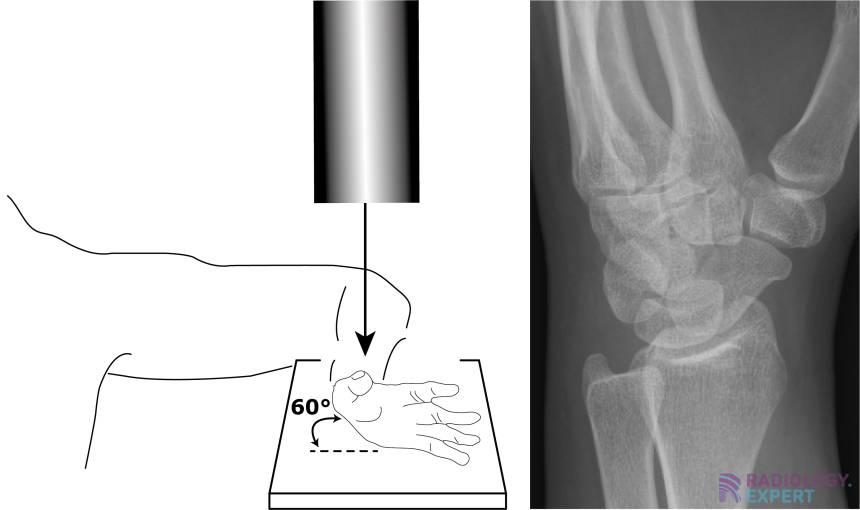

From www.radiology.expert

XWrist X Wrist Instructions High blood pressure can cause stroke, heart attack and dementia, to name a few. Please read the user manual for clear instructions on how to accurately measure your bp. X Wrist Instructions.